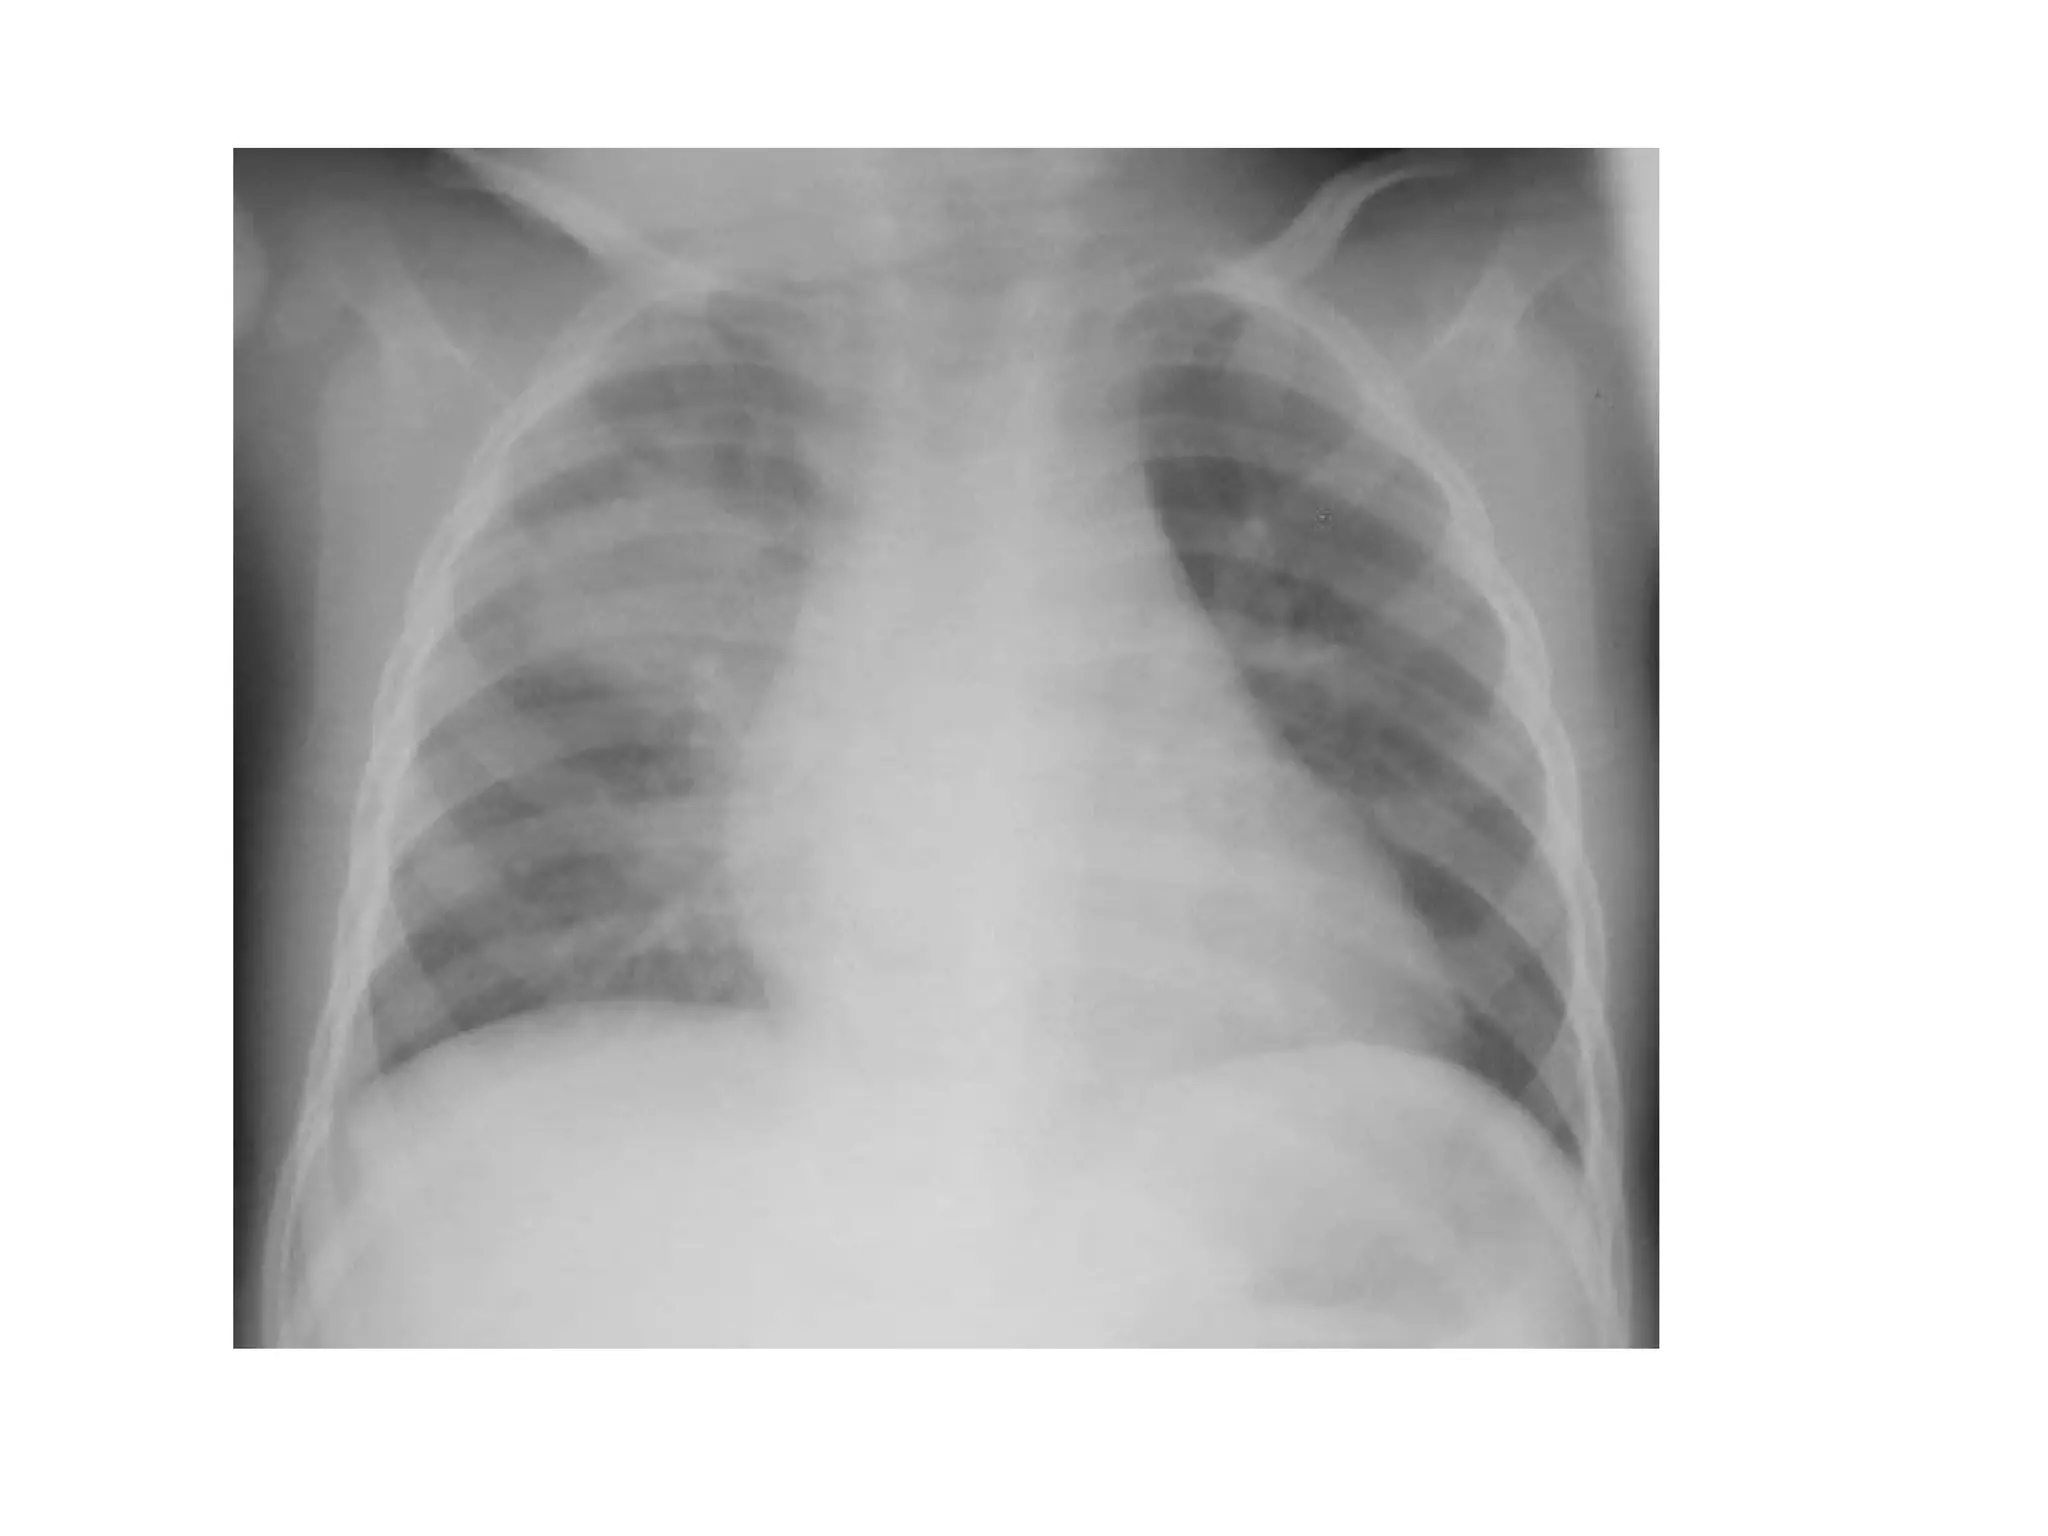

Interpretation of abnormal film

• Radiological signs

The silhouette sign is the loss of an interface

by adjacent disease, when air in the

alveolar space is replaced by fluid or soft

tissue, there is no longer a difference in

radiodensity between that part of the lung

and the adjacent structures. Therfore the

silhouette is lost and the silhouette sign is

present.

Interpretation of abnormalfilm • Radiological signs The silhouette sign is the loss of an interface by adjacent disease, when air in the alveolar space is replaced by fluid or soft tissue, there is no longer a difference in radiodensity between that part of the lung and the adjacent structures. Therfore the silhouette is lost and the silhouette sign is present.